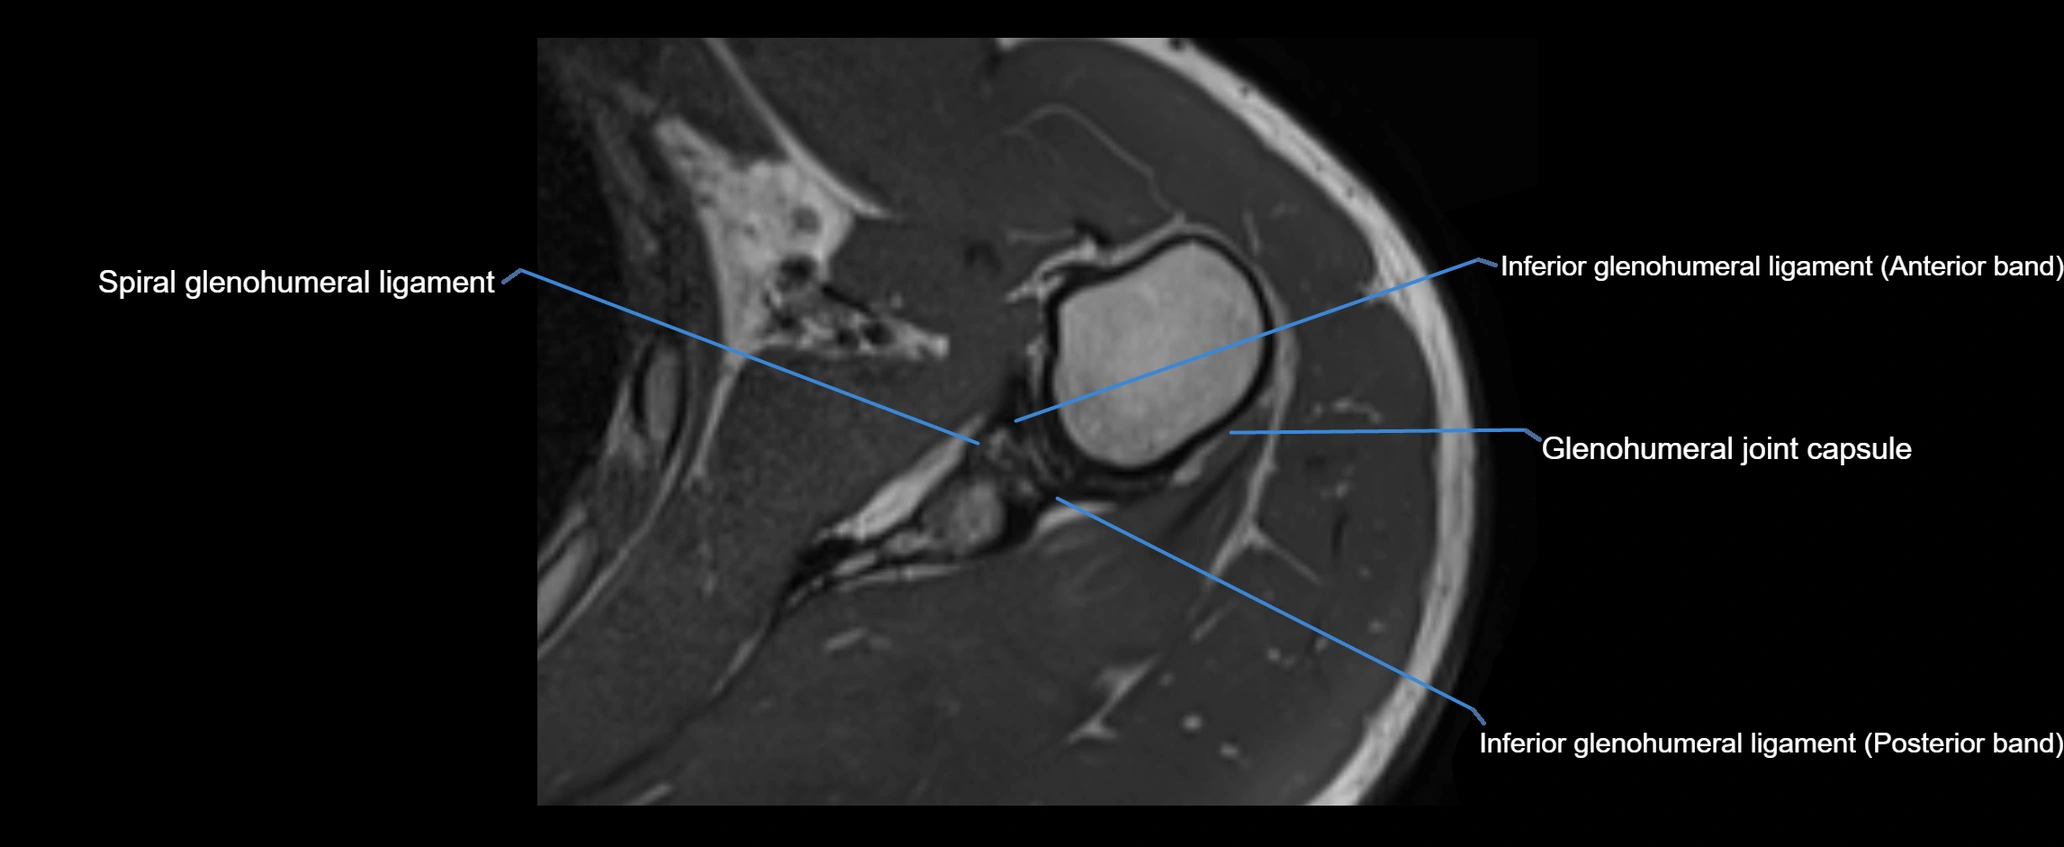

CT image

image